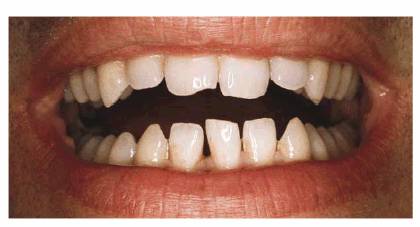

PROBLEM: A 20-year-old female presented with diastemas between her

maxillary lateral and central incisors (Figure 23-16A). She had a poorly fitting crown on the

Figure 23-16A and B: This 20-year-old student was unhappy with the appearance of her smile. In addition to the multiple spaces, there was a labial flare to the teeth that made them look shorter than they actually were.

TREATMENT: In cases where diastemas are evenly distributed between the

central and lateral incisors (Figure 23-16B), the best solution is laminating or crowning

all four anterior teeth. If only the central incisors were laminated or

crowned, the result would be less than ideal due to the overly contoured

appearance of the centrals. Proportionally contoured and shaped crowns were

constructed for the incisors and seated in place (Figures 23-16C, and 23-16D).

Figure 23-16C: Crowning the four maxillary incisors enabled the spaces to be closed and created better proportion between the central and lateral incisors.

Figure 23-16D: This close-up view shows the improved interincisal distance achieved.

RESULT: As previously stated, orthodontics is the preferred treatment of

choice in closing diastemas involving normal-sized teeth. However, when

correction by restoration is chosen, it is best to use an even number of teeth

to close diastemas. Although the above case was successfully treated with four

porcelain-fused-to-metal crowns, porcelain laminate veneering would probably be

the treatment of choice today.